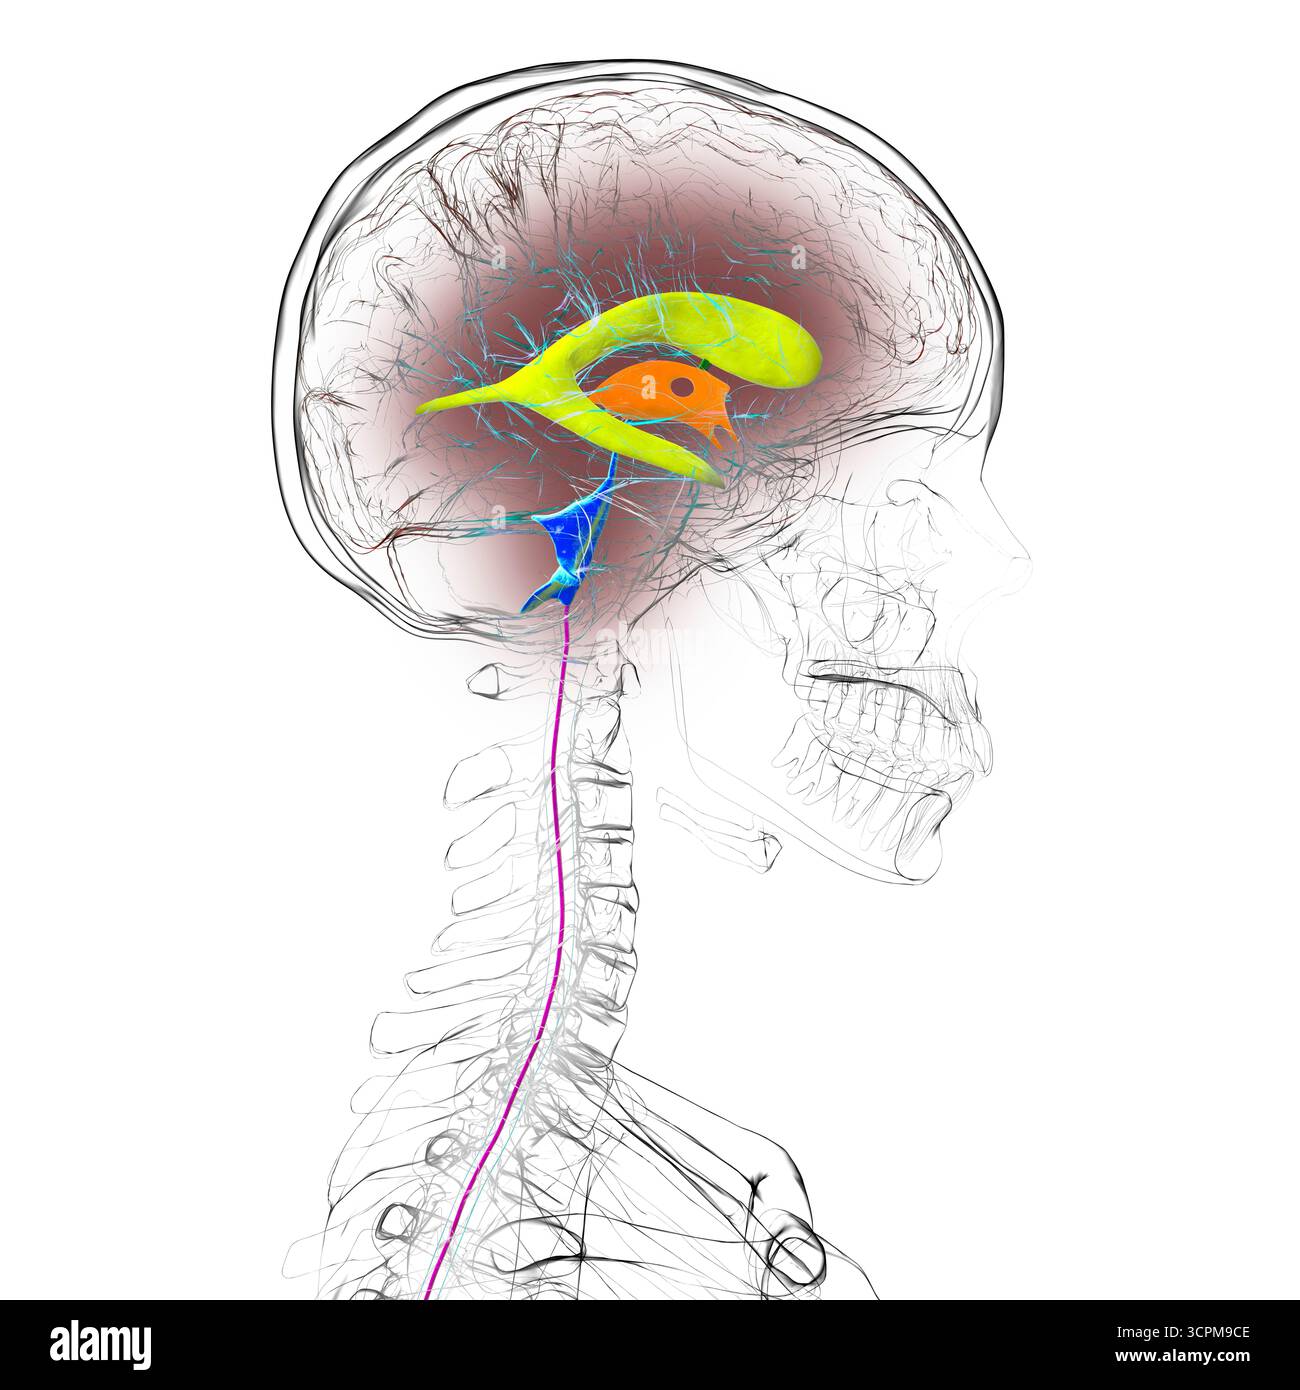

RF3CPM9D1–Abbildung des menschlichen Gehirns mit farbigen Ventrikeln: Lateral (gelb), dritter (orange), vierter (blau), interventrikuläres Foramen (grün), cerebral

RF3CPM9CD–Abbildung des menschlichen Gehirns mit farbigen Ventrikeln: Lateral (gelb), dritter (orange), vierter (blau), interventrikuläres Foramen (grün), cerebral